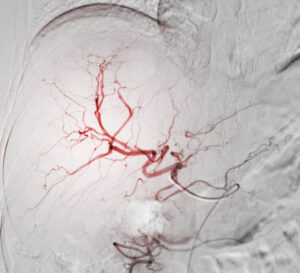

Les radiologues interventionnels utilisent des techniques d’imagerie (échographie, scanner, angiographie) pour réaliser des procédures mini-invasives à visée thérapeutique qui viennent en complément ou en alternative à la chirurgie.

Ces techniques permettent de traiter diverses pathologies sans nécessiter de grandes incisions, les patients n’ont donc pas de cicatrice au décours de l’intervention. Les procédures de radiologie interventionnelle sont souvent moins risquées et plus rapide que la chirurgie traditionnelle.

Cerveau/Cou